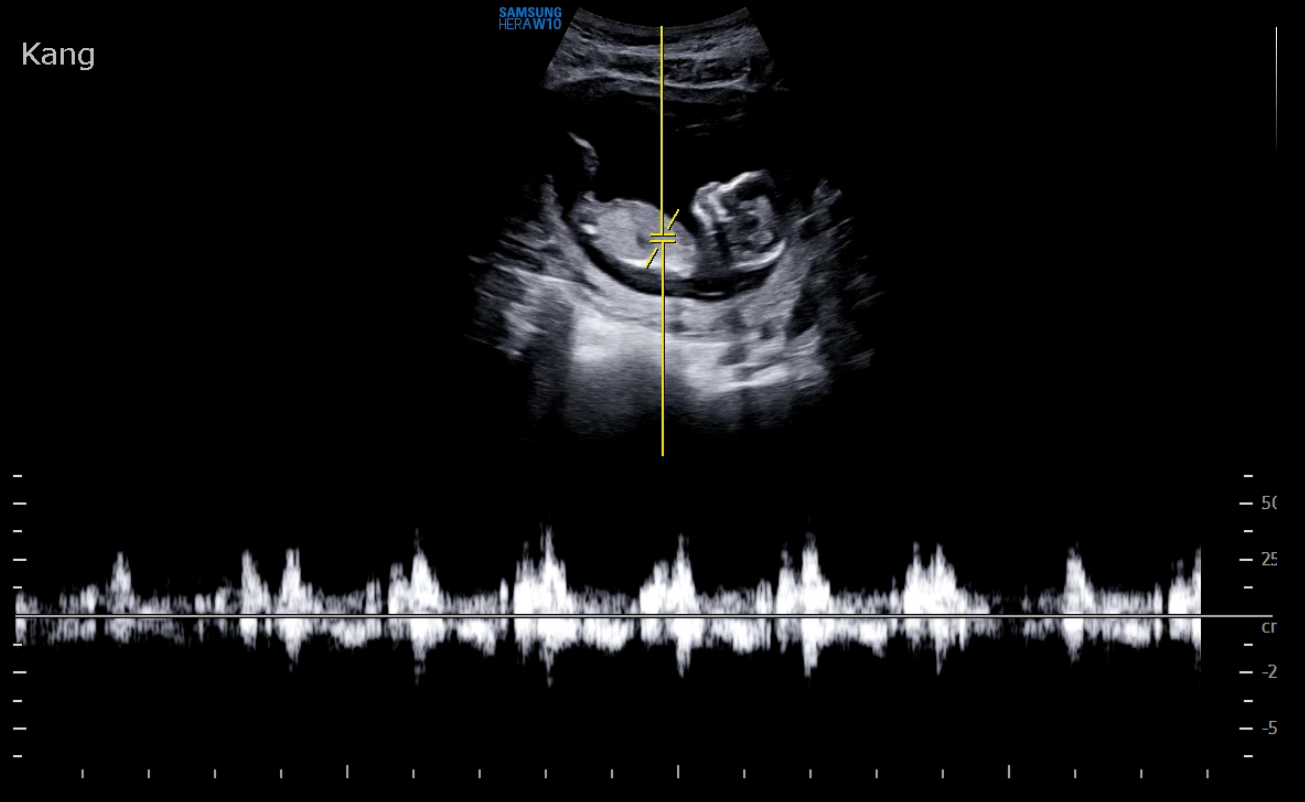

일단 심장부터 확인했고, 분당 150회 정도로 잘 뛰고 있었다. 이전에는 분당 180회였는데 아무래도 커가면서 조금씩 심장속도가 다시 느려지는 것 같다.

탯줄에 혈관이 제대로 형성됬는지도 봤고

하체를 통과하는 동맥과 정맥도 잘 있는지 확인했다.

마지막으로 엄마의 자궁내 혈관도 멀쩡한지 잘 확인한 후 초음파로 검사하는 항목은 끝!